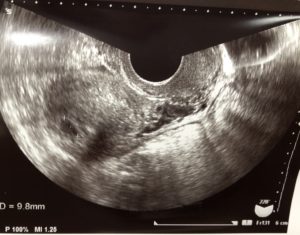

フライング検査早くやり過ぎてその後の時間が長かったですけど、ようやく胎嚢確認出来る時期になりました。

子宮外妊娠では無いか…胎嚢が週数通りの大きさか…胎嚢は1つなのか…

そして…ありました!

週数通りの胎嚢が!

今のところ1つ。

でもまだこれから見えてくる可能性もあるとの事。

次の診察で胎芽と会えるといいなぁ。